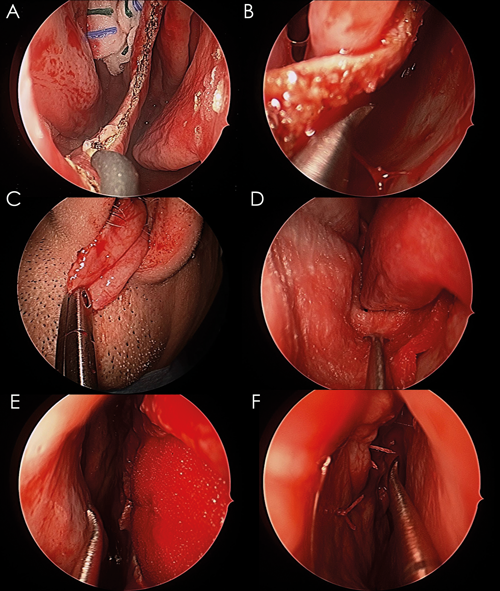

A pedicled flap based on the anterior ethmoid artery is used to repair the perforation. A monopolar needlepoint tip diathermy (Megadyne 0016AM, Mathi, Italy) is used to mark out the vascular pedicle across the posterior limit, lateral limit on the floor of the nose, extending within the inferior meatus, superior septum margins as well as separating the perforation margins (see Figure 2A). The extension and location of this mark depends on the size and location of the perforation. However, preparing an oversized flap is crucial for a successful outcome, and may feel uncomfortably large for a non-skull base surgeon.

Figure 2. (A) A monopolar needlepoint diathermy is used to separate the margins of the perforation; (B) A pedicled flap is raised from the lateral wall of the nasal cavity; (C) The pedicled flap is mobilised to the upper lip; (D) collagen matrix covers the exposed areas on the floor and lateral wall of the nasal cavity; (E) An endoscopic view of the contralateral septum showing the collagen matrix graft filling the perforation; (F) The final outcome after rotating and suturing the pedicled flap.

The mucoperichondrium/mucoperiosteum around the perforation is separated from the cartilage or bone underneath, exposing as far as the sphenoid rostrum, the superior part of the septum and the nasal floor. A hemitransfixion incision, on the ipsilateral side to the AEA flap is performed to connect the caudal end of the septum with the perforation in order to insert a collagen matrix scaffold (DuraMatrix Stryker, Kalamazoo, USA) in between the cartilage and the mucosa.

The AEA flap is raised (see Figure 2B) and relocated posteriorly in the nasal cavity to avoid trauma and allow adequate space to place the collagen matrix sheet. It is important that the flap has enough mobility to reach the upper lip (see Figure 2C). The collagen matrix graft is inserted ipsilaterally and placed between the cartilage/bone and mucosa (see Figure 2D). Collagen matrix facilitates healing and regeneration of the host tissue, as well as acting as a scaffold for the new mucosa. It also protects exposed bone on the floor of the nasal cavity.

Initially, the flap is sutured in the anterior edge of the perforation with vicryl rapide 5/0 13mm (Ethicon, Johnson & Johnson, Somerville, New Jersey, USA). Several simple sutures are placed in the superior, inferior and posterior edges of the perforation (see Figure 2E). One or two through and through sutures only are used to reduce dead space and stabilise the layers used to repair the defect (see Figure 2F).